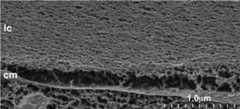

Figure 3.

A cryo-SEM image (35,000X) showing lens capsule (lc) slightly separated from an epithelial cell membrane (cm). The meshwork structure of the capsule is apparent.